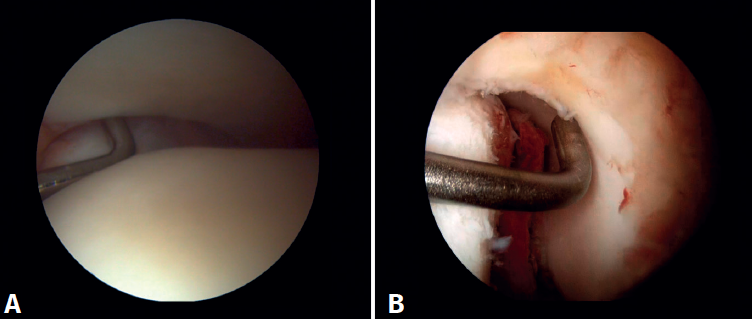

Evaluación artroscópica de la sindesmosis

Desde el portal anteromedial tenemos una visualización directa de las fibras distales del LTPA. Una desinserción de estas fibras no se traduce siempre en inestabilidad de la sindesmosis, pero nos obliga a comprobarlo. Los autores preferimos la evaluación del plano coronal de la sindesmosis. Introducimos el artroscopio en la articulación tibioastragalina dirigiendo la cámara hacia craneal. De este modo, tenemos una visión directa de la articulación tibioperonea distal. Entonces evaluamos la estabilidad intentando introducir el palpador en la articulación. Si es posible hacerlo, catalogamos la lesión de la sindesmosis como inestable (Figura 6A).

Evaluación artroscópica del ligamento deltoideo

Existen múltiples métodos para evaluar la inestabilidad del complejo medial; mediante los portales anteriores del tobillo es posible valorar la estabilidad del ligamento deltoideo en su plano principal de acción, correspondiente al plano coronal. Chun et al.(20) describió inestabilidad cuando es posible introducir un palpador artroscópico en el espacio medial tibioastragalino (Figura 6B). Vega et al.(21) describió que, en la mayoría de las lesiones, la porción más anterior del ligamento deltoideo está desprendida del maléolo medial, mientras que sus inserciones proximales permanecen íntegras. En esta situación se puede introducir el palpador artroscópico entre la pared medial del maléolo interno y las fibras profundas del deltoideo.

Figura 6. Maniobras para evidenciar inestabilidad ligamentosa. A: lesión de la sindesmosis que permite la introducción del palpador en la tibioperonea distal; B: lesión del deltoideo que permite la introducción del palpador en el espacio medial tibioastragalino.